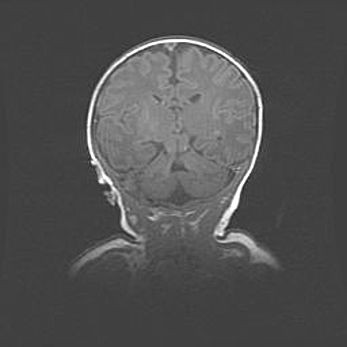

Лейкомаляция с кистозно-глиозной дегенерацией головного мозга.

Возраст: 2 месяца 25 дней

Вес: 6400 г

Окружность головы: 40 см

Срок гестации: 41 неделя

Лейкомаляцию относят к ишемически-гипоксическим повреждениям головного мозга, диагностируемым у новорожденных. При лейкомаляции в головном мозге обнаруживают очаги некроза, возникшие после тяжелой гипоксии и нарушения кровотока. В процессе морфогенеза очаги проходят три стадии: 1) развития некроза, 2) резорбции и 3) формирования глиозного рубца или кисты. Перивентрикулярная лейкомаляция (ПЛ) встречается примерно в 12% случаев среди новорожденных, обычно – у недоношенных детей, причем, частота ее зависит от массы, с которой младенец появился на свет. Наибольшее число малышей страдает лейкомаляцией, если масса при рождении 1500-2500 г.